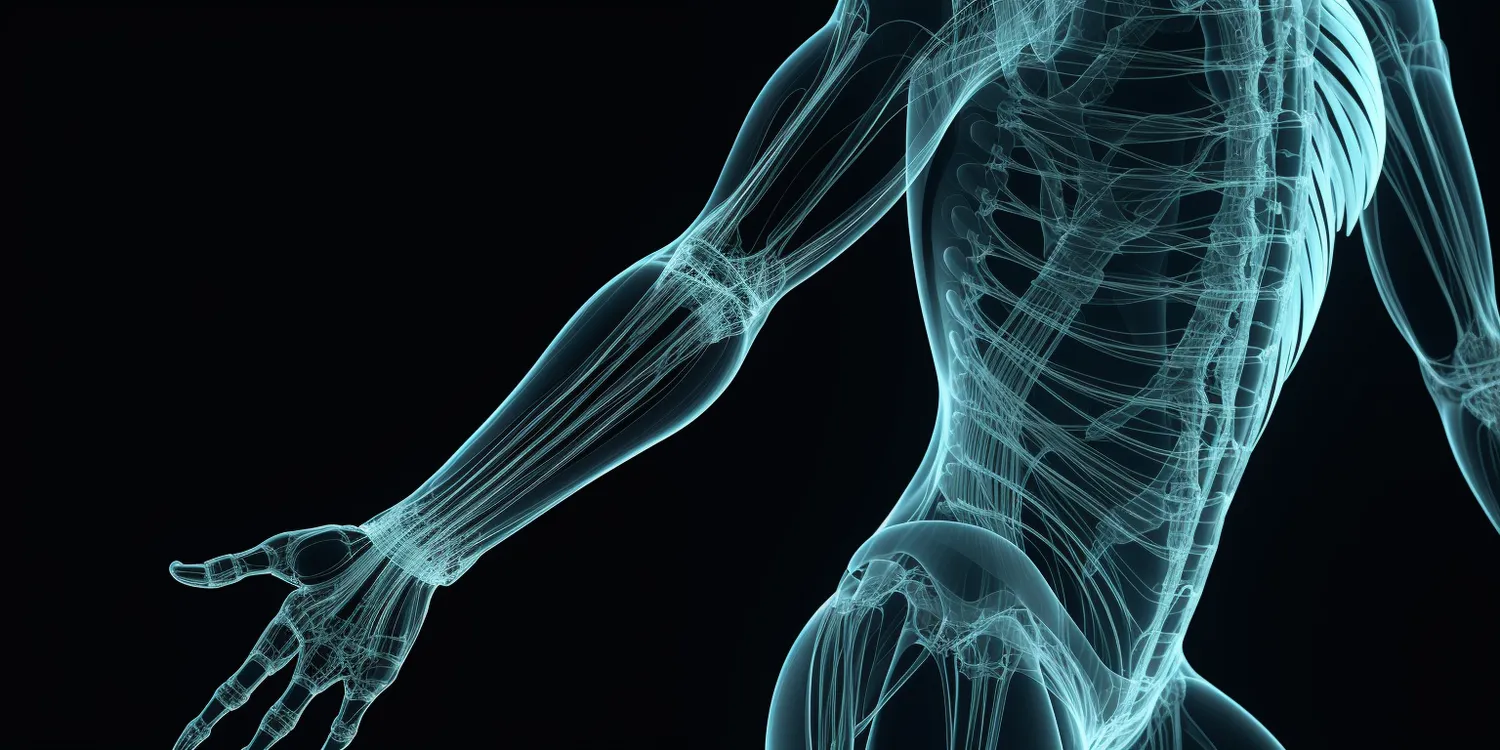

Rehabilitacja Warszawa

Rehabilitacja w Warszawie oferuje szereg różnorodnych metod, które mają na celu przywrócenie sprawności fizycznej oraz…